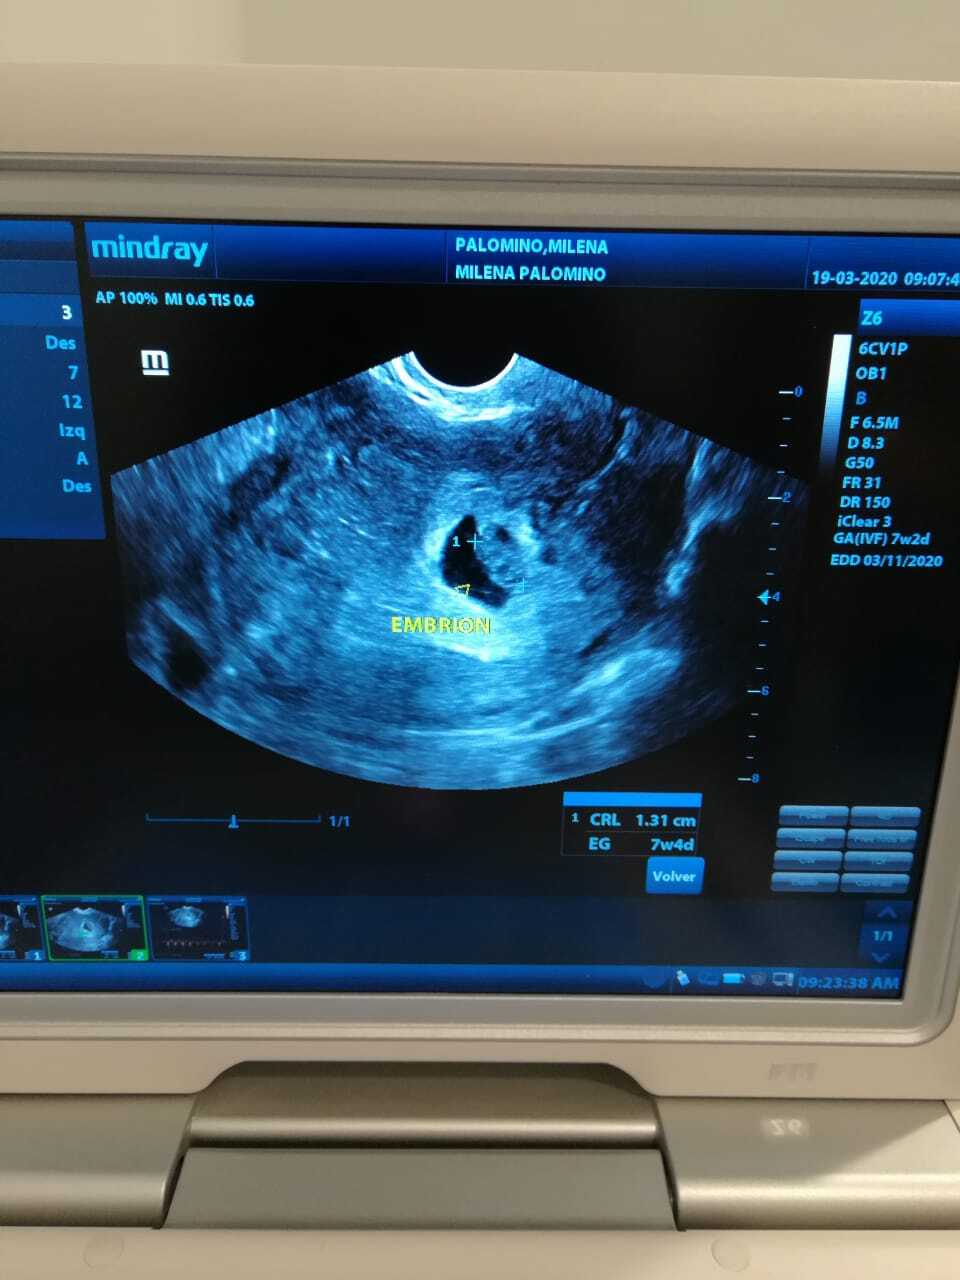

ULTRASON